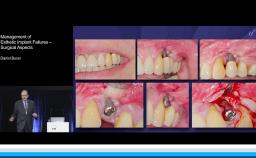

Dean Morton discusses how to plan for success rather than failure and how to effectively manage problems when they occur.

The etiology of tooth loss and the goals of therapy provided by the implant clinician are also covered. The lecture includes excellent use of clinical cases to highlight common complications in implant dentistry to include biological, mechanical, and technical complications and how to avoid them.